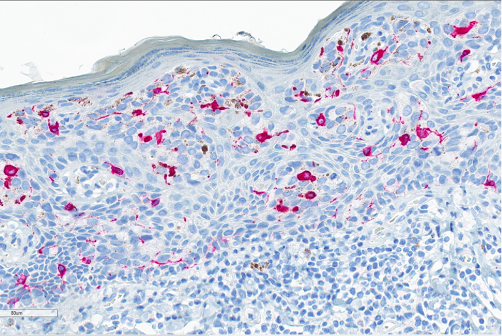

Figure 6. Immunohistochemistry. SOX10, a nuclear stain, was interpreted as negative in the cells of interest. The stain does highlight benign melanocytes.

Figure 7. Immunohistochemistry. Melan-A, a cytoplasmic stain, was interpreted as negative in the cytoplasm of cells of interest but highlights the intraepithelial melanocytes.

In some cases, there may be melanin pigment throughout the epidermis and dermis, which gives rise to a melanoma differential. In this situation, SOX10 and Melan-A will stain the background melanocytes; however, the Paget tumor cells will be negative. Other differentials include vulvar intraepithelial neoplasia, HPV-independent (dVIN), high-grade squamous intraepithelial lesion (HSIL) with pagetoid spread, and secondary Paget disease. dVIN can microscopically look like Paget with the nested, pale tumor cells, as well as mucinous differentiation, however, it will be negative for CK7 and GCDFP-15. HSIL can mimic Paget with mucinous areas, melanin pigment, and pagetoid spread too. To best differentiate HSIL from Paget, high-risk HPV ISH is useful, as it will be positive in HSIL and negative in Paget. The last differential is secondary Paget, which is much less common and originates in another location before metastasizing, such as the rectum, cervix, or bladder. These would stain for CDX2, CK20, or uroplakin-3, respectively.